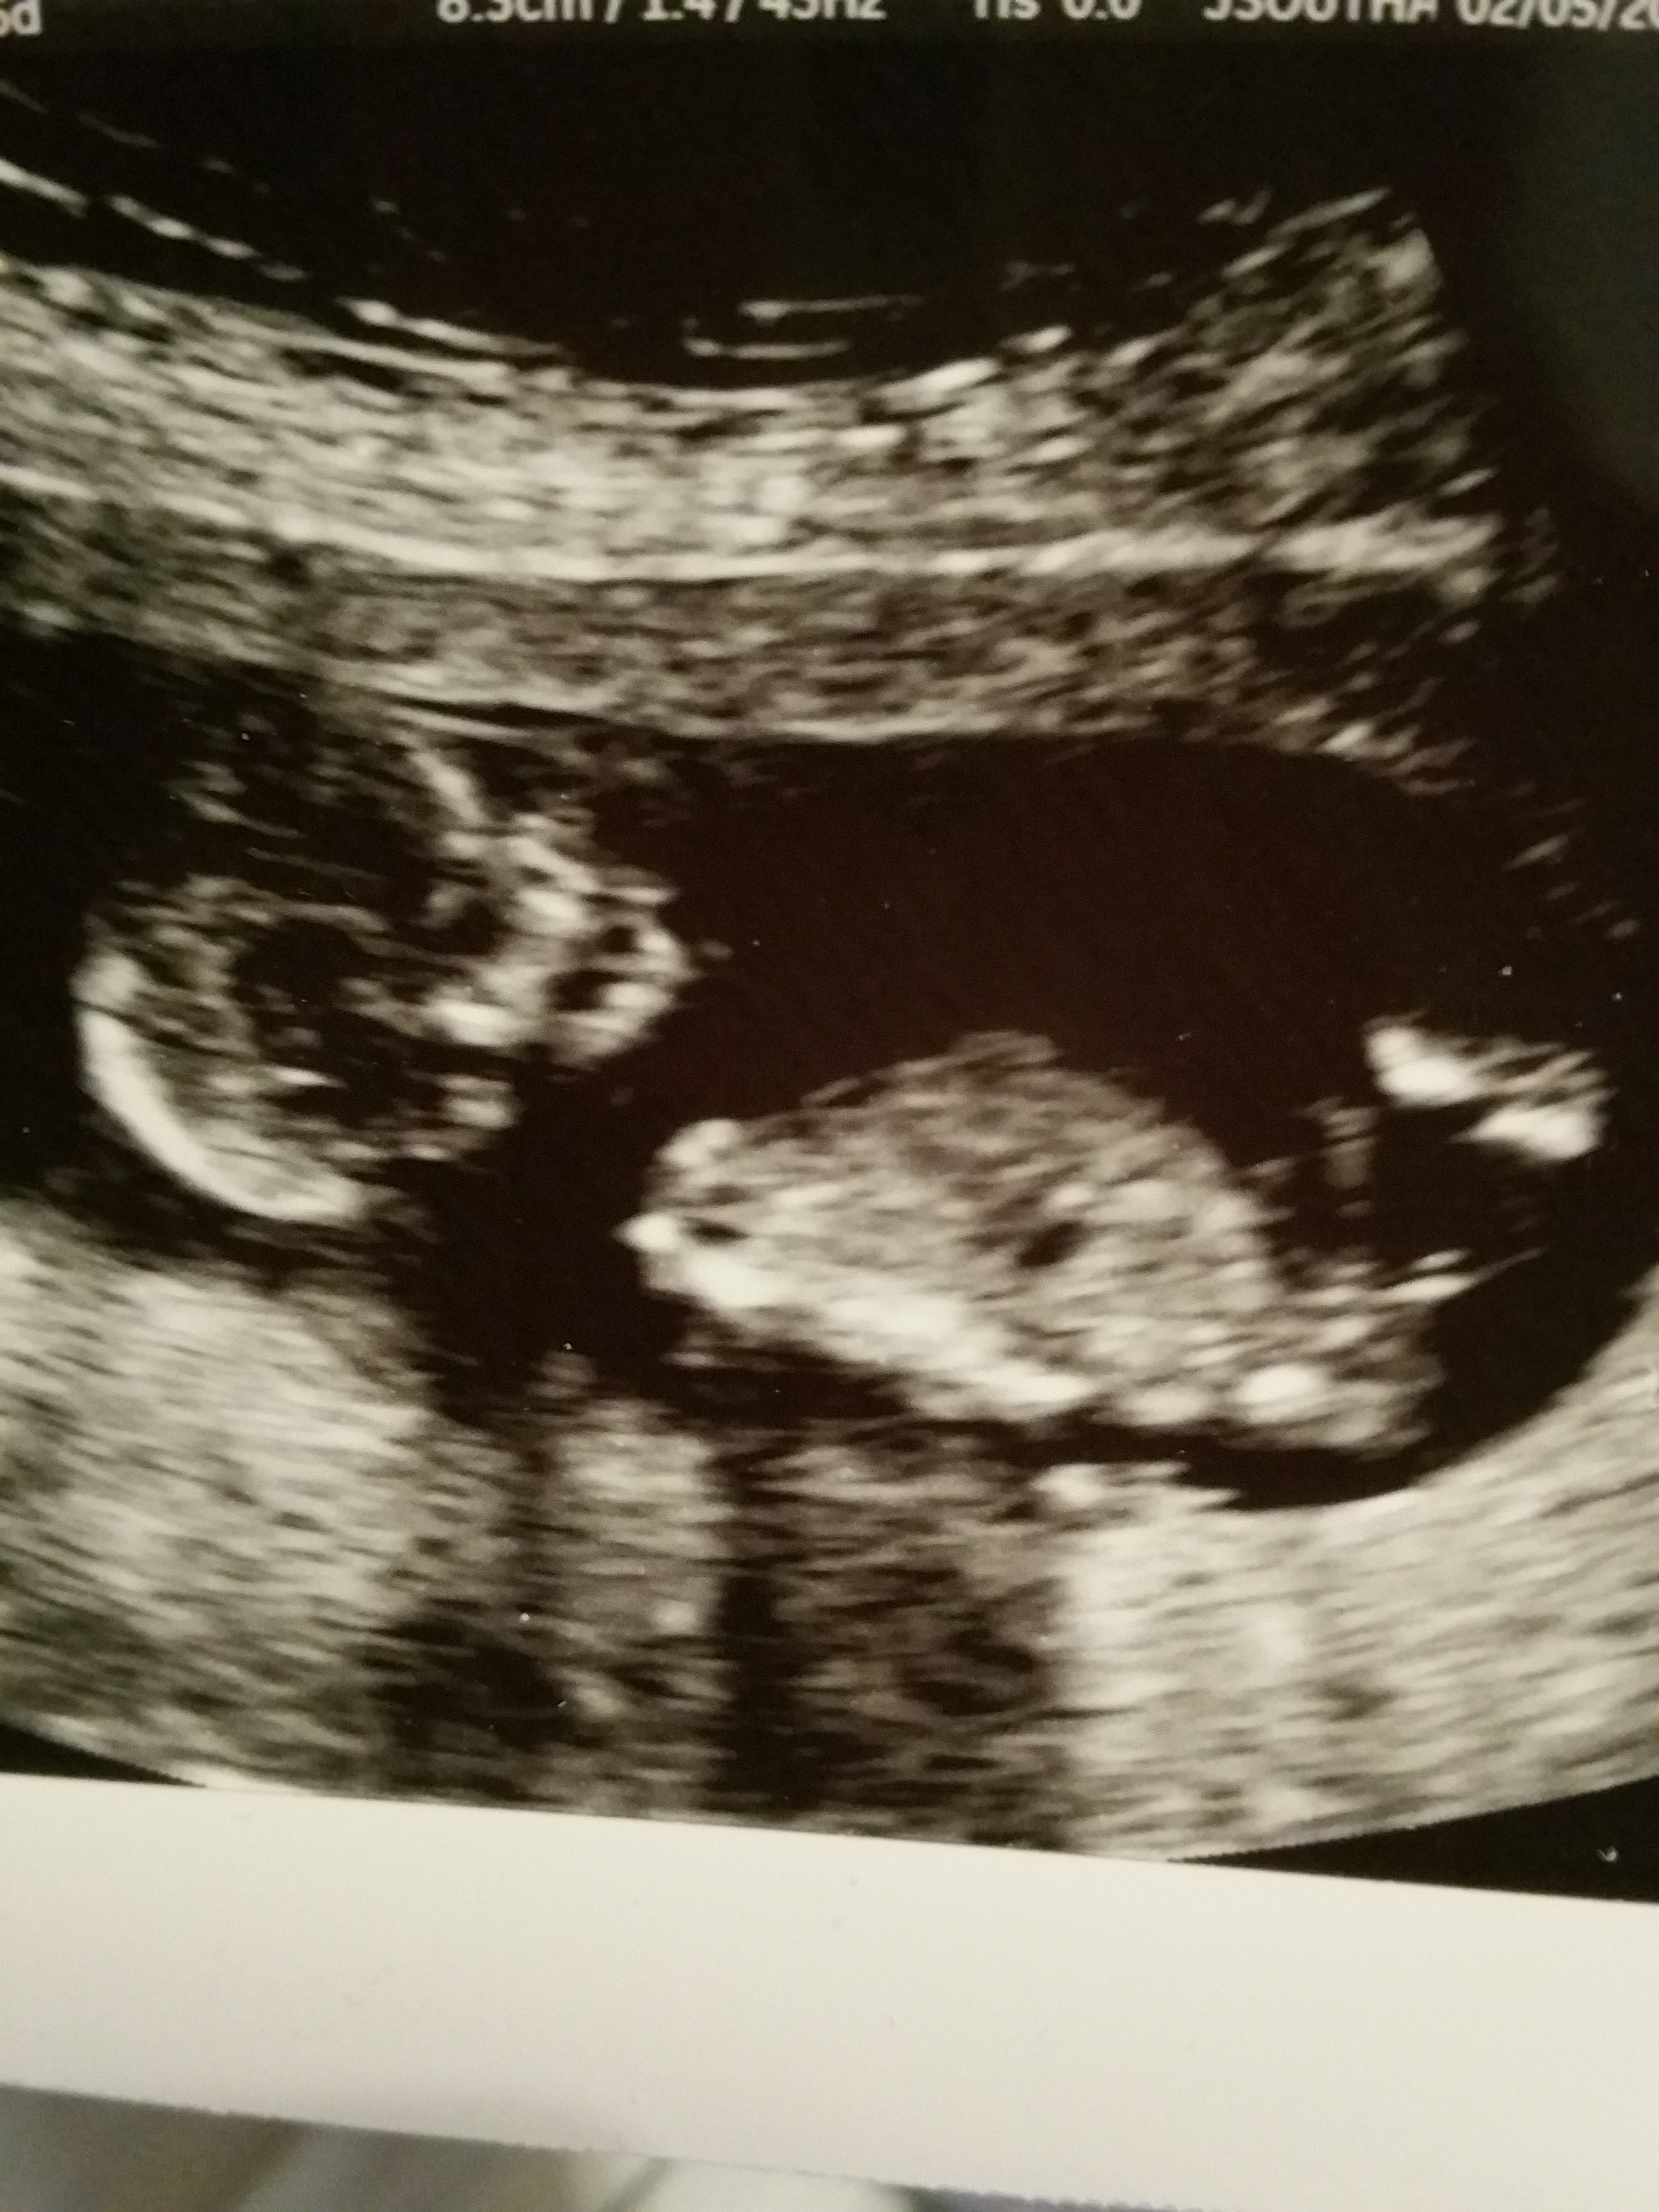

Hi everyone. Was hoping to have some guesses on what my little one is. These were done at exactly 13 weeks. Thanks so much! Attachment 23663Attachment 23662

Omg I'm sorry! I'm not sure how to take out the third sideways picture!

Boy guess

Guessing boy from the last picture!